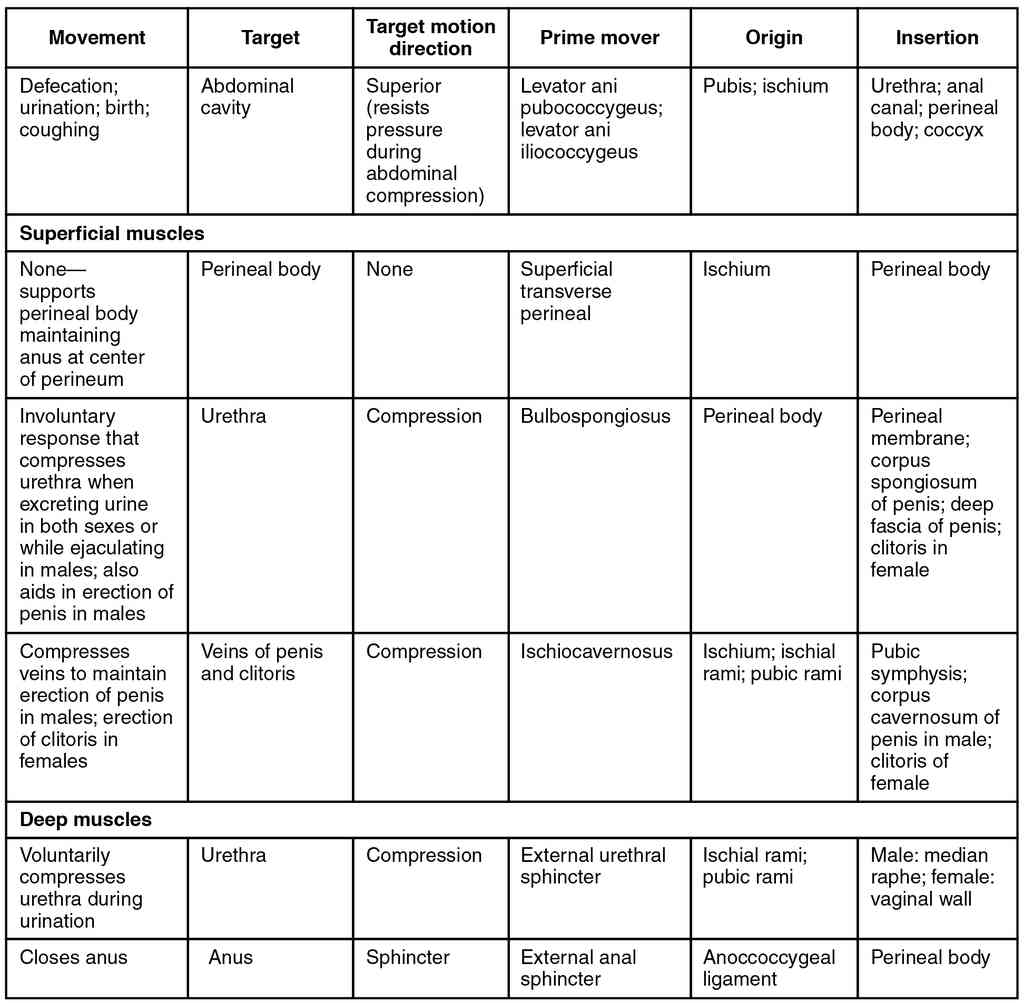

This page is under construction. For now, it is just a resource of the images found in the OpenStax Anatomy and Physiology Handbook. It wil slowly change into a revision tool. Each slide has a number. Use this to refer to the slide. When completed, it will have an unlabelled section, with labelled slides in parallel. On the unlabelled slides, write your answer and use the labelled slide to assess yourself. Keep track by also noting the number on each slide. Improvement at each attempt is important, more so than full marks on a first attempt.